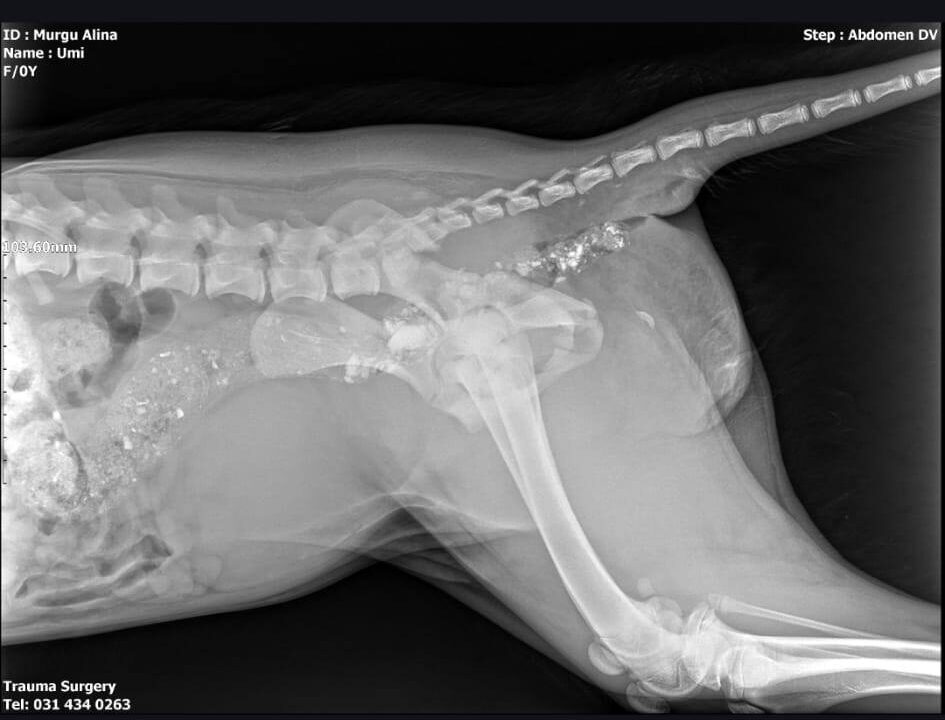

Elle a eu la malchance d’être heurtée par un camion, et Alina l’a emmenée mercredi pour des radiographies. Umi avait une fracture et une disjonction de la hanche, et la queue cassée au niveau du sacrum. Elle a subi une chirurgie : à une patte, elle a eu une résection de la tête fémorale, et à l’autre patte, une broche a été posée pour fixer la partie cassée de la hanche. Maintenant, elle est sous traitement et Alina espère qu’elle récupérera l’usage de ses pattes arrière et qu’elle ne souffrira pas d’incontinence.